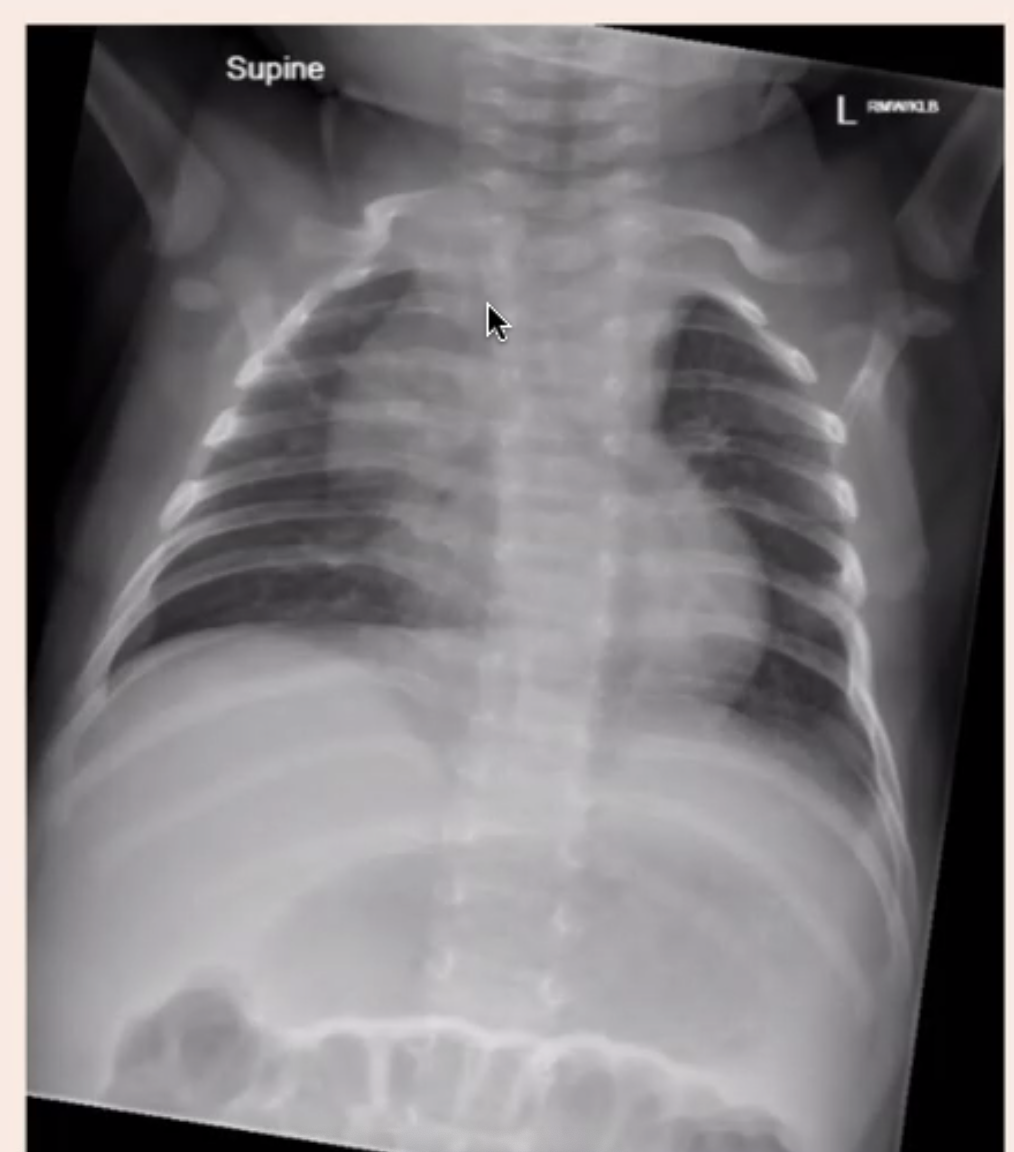

How does the thymus typically appear on a chest xray in kids?

• Triangular sale frequently towards the R) of the mediastinum

• Relatively large in infancy, grows considerably in neonates, largest weight in adolescence

• Two lobes, often assymetric, cab be separated by a 3rd intermediate lobe

• Often sicks in the neck/upper chest (thyroid gland to 4th ICS)